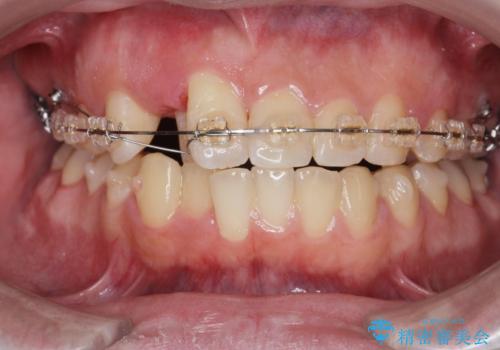

- 矯正装置

- ワイヤー矯正 → インビザライン

- 治療期間

- 3年

- 治療回数

- 30回以上

見た目、噛み合わせが大きく改善し、大変喜んでいただくことができました。